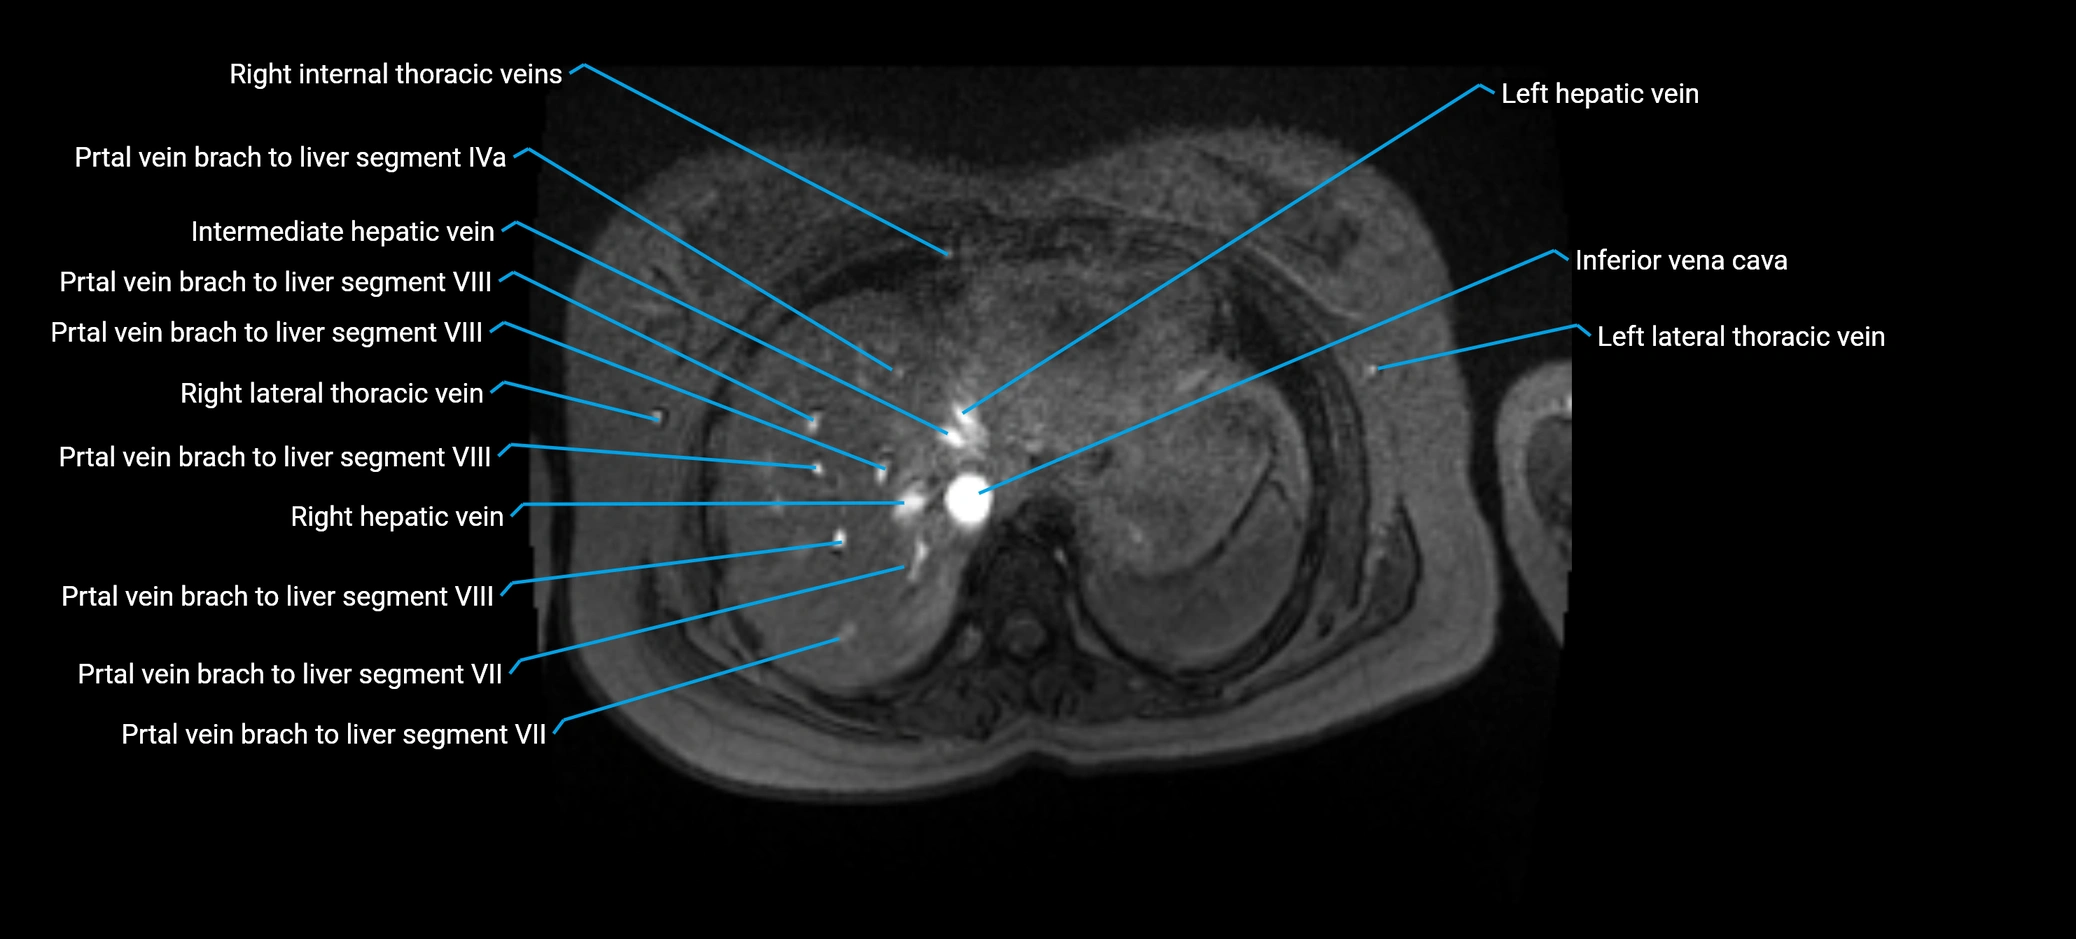

MRV TOF (Time-of-Flight MR Venography):

• Appears as a bright, high-signal vascular channel representing flowing blood

• Clearly shows branching pattern of right portal vein into anterior and posterior branches

• Best in coronal or axial reconstructions for segmental mapping

• No need for contrast, relies on flow-related enhancement

MRI image

image